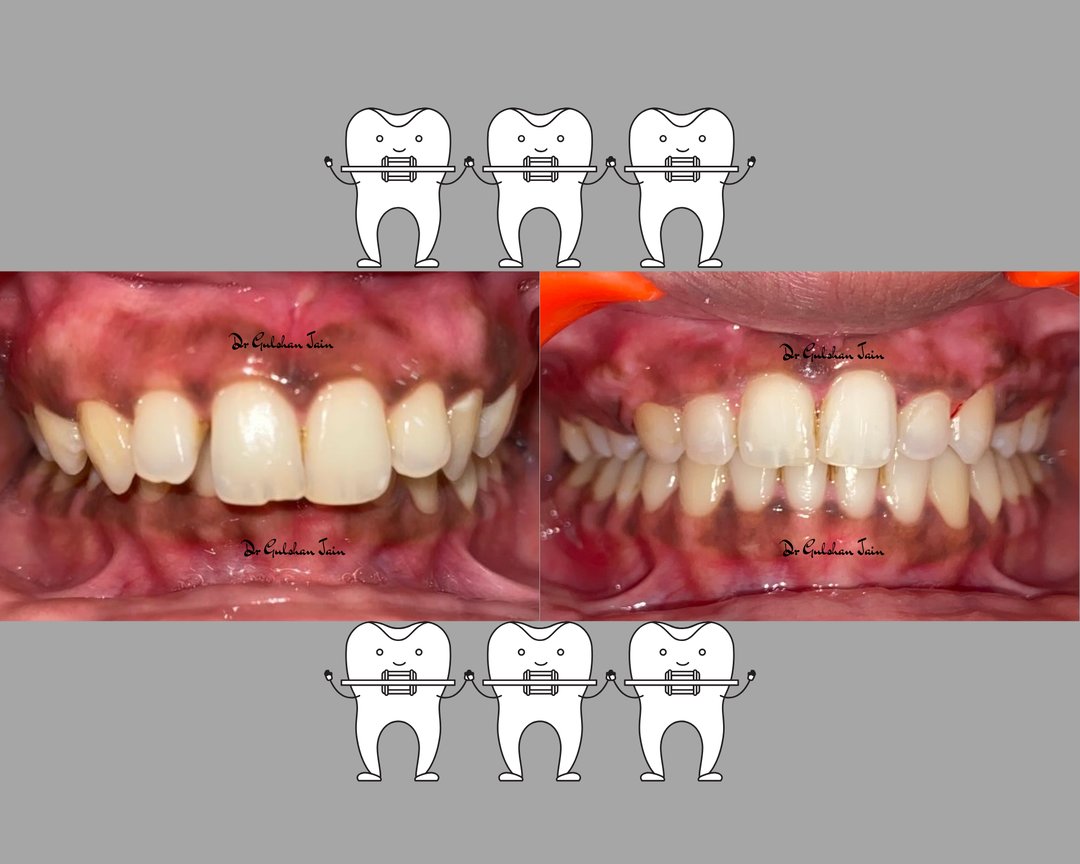

Welcome to our gallery

See how our company transforms ideas into reality. This gallery is a visual testament to our work and achievements.